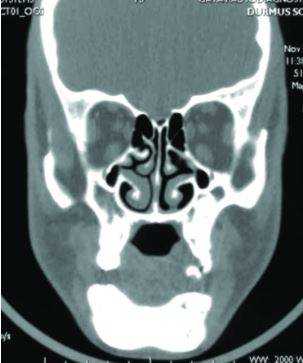

КТ челюсти и гайморовых пазух

Иногда пациент обращается к стоматологу из-за проблем с зубами, а врач назначает КТ челюсти и гайморовых пазух. Не переживайте, это не попытка навязать дополнительные обследования - часто без сканирования смежных зон просто не обойтись.

Заболевания челюсти и гайморовых (верхнечелюстных) пазух связаны с особенностями их морфологического строения. Корни зубов моляров, а иногда и премоляров (4,5,6,7 и зубы мудрости) проникают в дно пазухи. Поэтому, при возникновении проблем с зубами, это сказывается на состоянии околоносовых пазух.

КТ челюсти и придаточных пазух

То есть ЛОР-заболевания могут быть тесно связаны со стоматологическими проблемами. И иногда требуется консультация двух специалистов: и стоматолога, и оториноларинголога.

Вследствие осложнений стоматологического лечения в пазухе носа могут быть инородные тела, остатки зубов, пломбировочный материал. Если такая неприятность возникла, то не обойтись без КТ, как челюсти, так и гайморовых пазух. Потребуется комплексная терапия - одновременное лечение и зубов, и синусов. В этой ситуации КТ дает панорамную картину, позволяет оценить масштабы проблемы и позволяет специалисту составить правильное лечение.